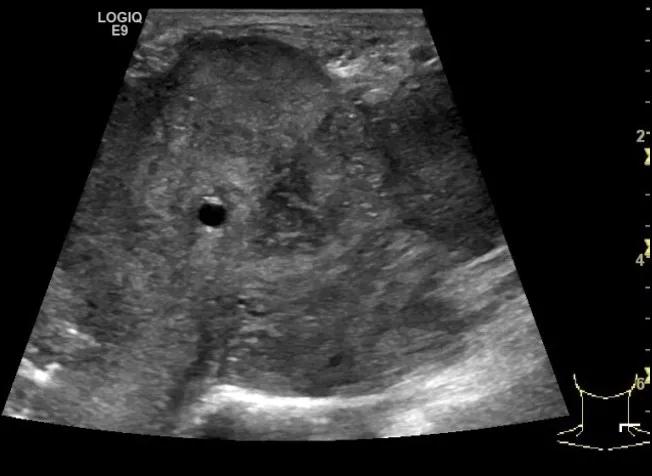

第四例是胸腺癌化妆包,术后、化疗之后淋巴结转移,肿块范围巨大,99mm*61mm,边界不清,呈浸润状,肿块包绕颈动脉,颈内静脉压闭,症状明显。由于患者放化疗也不敏感、血供非常丰富,于是采取多点姑息性消融。姑息性消融后未实现完全消融,病灶大片坏死,肿胀疼痛得到明显的缓解,后续患者未再来复查。

(病例4图例)